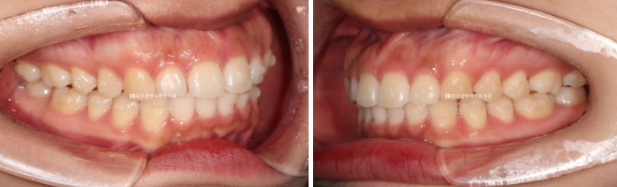

24.02~24.10

뻗쳐있던 앞니 각도는 좋아졌고

공간도 깔끔하게 모아졌으며 배열도 좋습니다.

앞니를 뒤로 넣을 때 단순 뒤로만 움직이는 것이 아니라 위로 올리면서 함입하며 넣었기에 잇몸 노출량도 소량 줄었습니다.

일자로 떨어지는 앞니 각도는 세련된 인상을 줍니다

원래 앞니 돌출때문에 입술부전증이 있었습니다만 앞니가 뒤로 들어가게 되면서 입술이 편하게 다물려집니다.